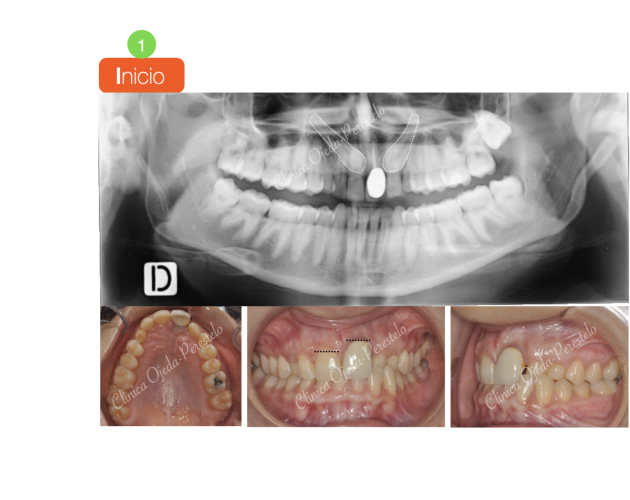

Premolar Mandibular Retenido (35) Casos de Éxito - Niños - Dientes Retenidos